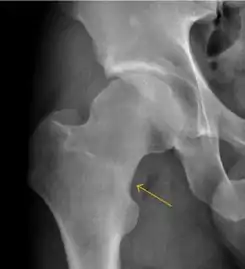

Plain radiography allows us to categorize the hip as normal or dysplastic or with impingement signs (pincer, cam, or a combination of both). Besides these, pathologic processes like osteoarthritis, inflammatory diseases, infection, or tumors can also be identified (Figure 1).[1]

Figure 1.

Radiography in normal hip

X-ray in pincer impingement type of hip dysplasia

X-ray of cam

Hip in osteoarthritis

Septic arthritis

X-ray in pediatrics